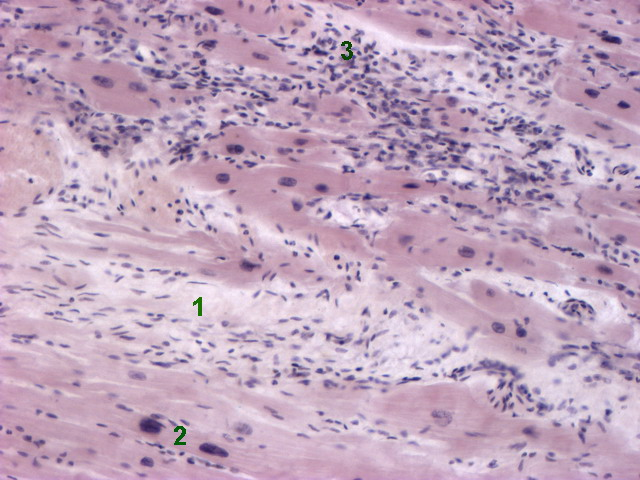

Межуточный миокардит: гистологические исследования